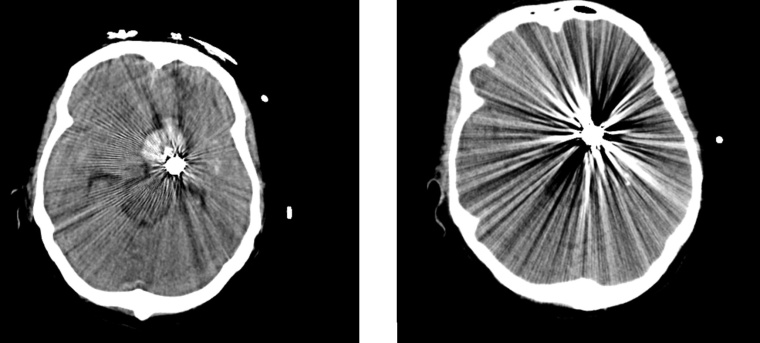

In der neuroradiologischen Versorgung von Aneurysmata werden spezielle Coils eingesetzt, die aus Platin mit Seidenanteilen bestehen – hierdurch entstehen mit herkömmlichen CTs in den Nachkontrollen massive Metallartefakte, die eine Beurteilung des Gewebes und der an das Aneurysma angrenzenden Gefäße in unmittelbarer Umgebung unmöglich machen bzw. sehr erschweren (Bild 1 a). Deutlich verbessert wird die Befundbarkeit mit SEMAR (Bild 1 b). In der postinterventionellen Kontrolle der meist intensivpflichtigen Patienten will der Kliniker in möglichst einem Untersuchungsgang komplexe Fragestellungen nach Vasospasmus/Blutung/Ischämie/Gefäßabbrüchen beantwortet haben. Diese teils hochkomplexen Fragestellungen können über die Ganzhirnperfusion in kürzester Zeit und mit hoher Detailgenauigkeit beantwortet werden. Durch die neue SEMAR-Technologie gelingt es auch, die unmittelbar an das gecoilte Aneurysma angrenzenden Gefäß und Hirnanteile in sehr guter diagnostischer Qualität darzustellen. Insbesondere die hohe Detailgenauigkeit der Gefäße war so mit herkömmlichen Geräten bisher nicht möglich und nur mittels invasiver Katheterangiografie darzustellen. Somit stellt die Kombination aus der Ganzhirnperfusion und der neuen Artefaktunterdrückung im klinischen Alltag einen enormen diagnostischen und klinischen Fortschritt und Mehrnutzen dar.

Erschwerend hat der Patient beidseitige Cochlea-Implantate (CI), so dass zum einen ausgeprägte Aufhärtungsartefakte die Diagnostik erschweren (Bild 2 a) und zum anderen eine alternative MRT-Untersuchung nicht möglich ist. In der anschließenden CT-Angiografie, als Spiral-CT gefahren, erschweren die Aufhärtungsartefakte eine genaue Lokalisation des Gefäßverschlusses (CTA Bild 2 b). In dem anschließend sekundär berechneten CTA-Datensatz (Bild 2 c) zeigt sich ein eindeutig zu diagnostizierender Verschluss der rechten A. cerebri media im M2-Segment als Ursache für die linksseitige Hemiparese. Die in der CTA noch ausgeprägten Aufhärtungsartefakte werden nach der SEMAR-Rekonstruktion deutlich reduziert, so dass hieraus auf vergleichbaren Schnittebenen ein klarer diagnostischer Zugewinn resultiert (Vergleich Bild 2 b und Bild 2 c). Zusätzlich kann in diagnostischer Qualität eine Ganzhirnperfusion errechnet werden, so dass die Frage nach einem Perfusionsmismatch ebenfalls beantwortet werden kann.